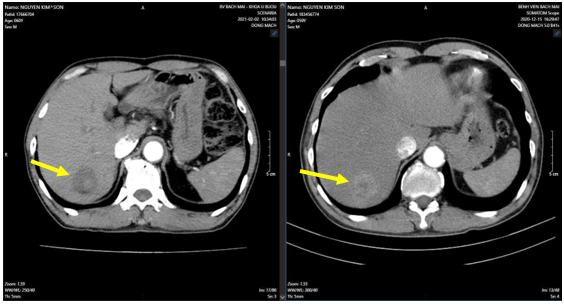

-  Chụp cắt lớp vi tính bụng: (Tháng 12/2020) Hình ảnh khối ngấm thuốc gan phải: Nhu mô phân thùy VII có khối kích thước 37x35mm, ngấm thuốc thì động mạch, ngấm thêm vào trung tâm thì tĩnh mạch cửa, vùng trung tâm không thấy ngấm thuốc. Gan:Kích thước bình thường, bờ đều. Sỏi túi mật. Sỏi thận phải. Nang nhỏ thận trái.

Hình 1: Nhu mô phân thùy VII có khối kích thước 37x35mm, ngấm thuốc thì động mạch, ngấm thêm vào trung tâm thì tĩnh mạch cửa,vùng trung tâm không thấy ngấm thuốc. (mũi tên vàng)